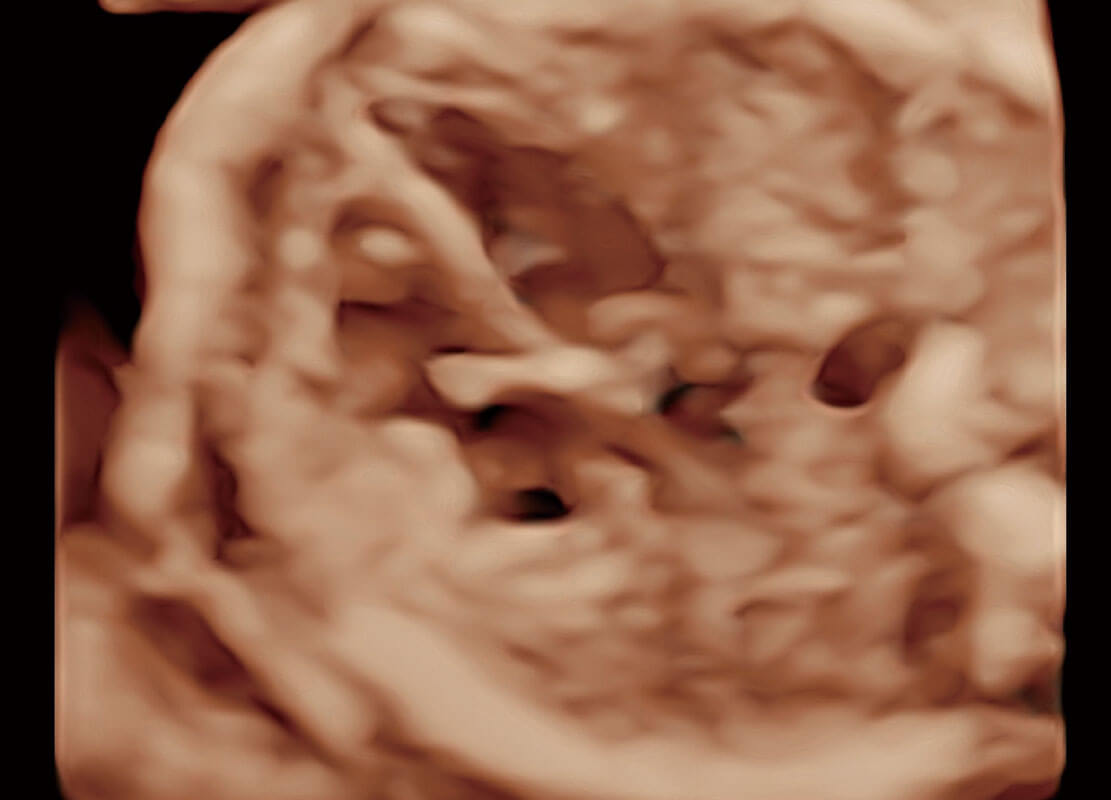

腔内三维-宫内节育器

腔内三维-光影成像

P60优异的图像质量搭载专科探头,在妇科基础疾病的诊断、卵泡生长的监测、输卵管通畅情况的判别等方面为您提供生殖应用方案。

腔内妇科-宫腔分离

腔内妇科-卵巢